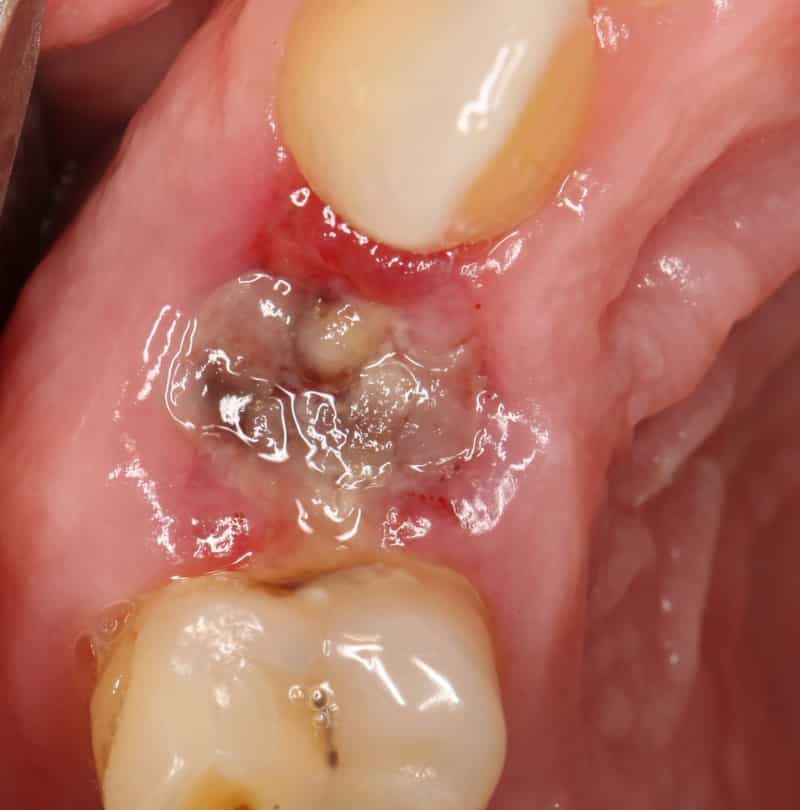

Скорость восстановления после удаления зуба зависит от нескольких факторов, включая физиологические особенности пациента, опыт врача, место удаления зуба и возможные осложнения операции. В некоторых случаях, когда зуб уже отсутствует или разрушается во время операции, стоматолог может прибегнуть к разрезанию десны, что может замедлить процесс заживления. После удаления зуба образуется кровяной сгусток, который играет роль барьера для защиты от инфекций. Этот сгусток необходимо оставить на месте, чтобы предотвратить воспалительные процессы. В течение нескольких дней сгусток меняет цвет и постепенно заживает, а открытая рана затягивается грануляционной тканью. Полное заживление мягких тканей обычно занимает около 2-3 недель, но процесс формирования новой костной ткани может продолжаться несколько месяцев. После удаления зуба может наблюдаться отёк десны, который обычно сходит через несколько дней.

Прежде всего, важно отметить, что не рекомендуется использовать перекись водорода и раствор соды для полоскания рта. Несмотря на их антисептический эффект, эти средства могут удалить кровяной сгусток, который выполняет защитную функцию. В результате десна останутся без защиты от инфекции.

- не следует вымывать кровяной сгусток из раны, достаточно просто подержать раствор во рту несколько минут и выплюнуть его;